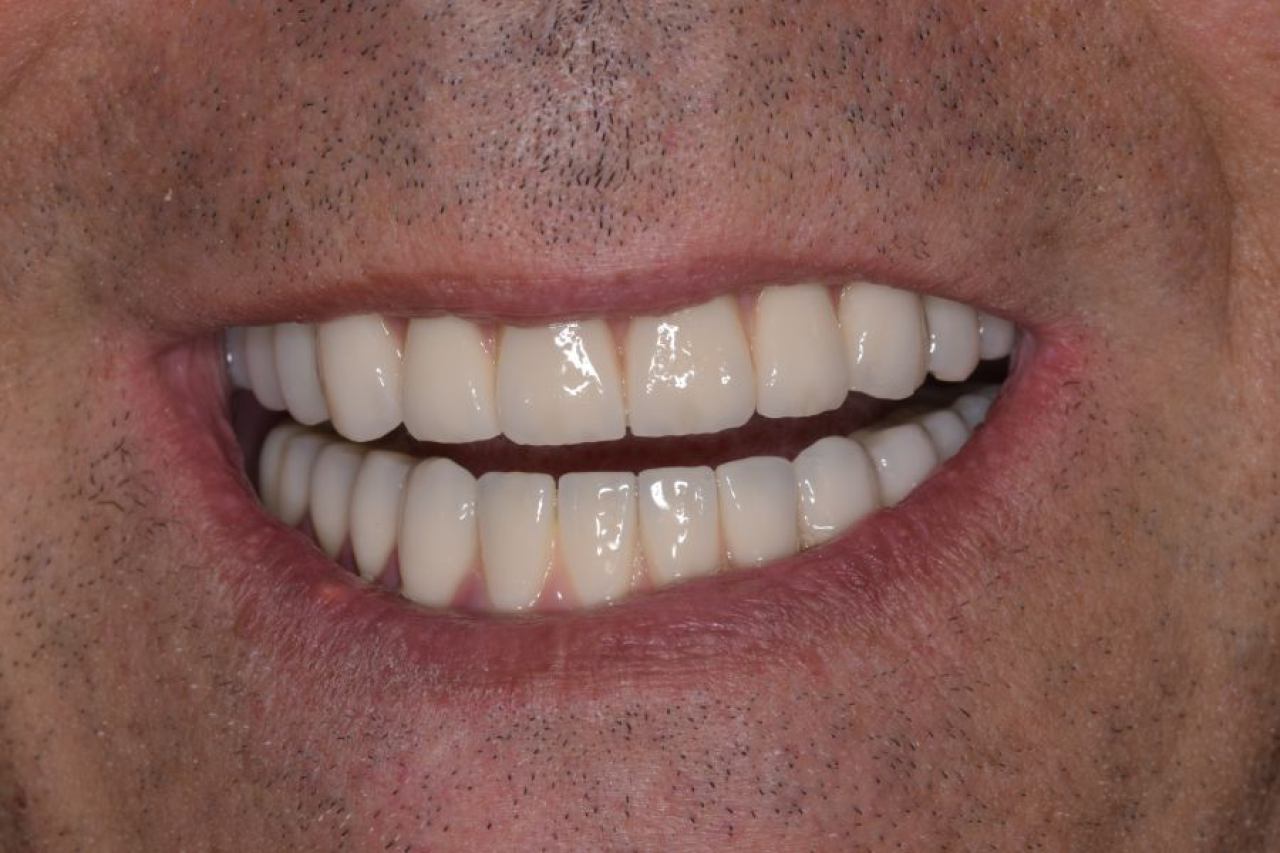

All On 4 i All On 6 fiksni mostovi na 4-6 implantata, omogućavaju da se brzo, ekonomično i efikasno pacijentu od bezube čeljusti omogući mastikatorna i estetska funkcija.

Protetika - mostovi i krunice

Dentalna protetika uključuje fiksne i mobilne radove kojima se nadoknađuje djelomična ili potpuna bezubost. Njihov cilj je povratiti funkciju žvačnog sustava i u konačnici, vrhunsku estetiku.

Marković Dental Clinic u svojoj ponudi ima metalkeramičke radove, potpunokeramičke radove, te u narodu zvane „bezmetalne", odnosno zirkonske radove.